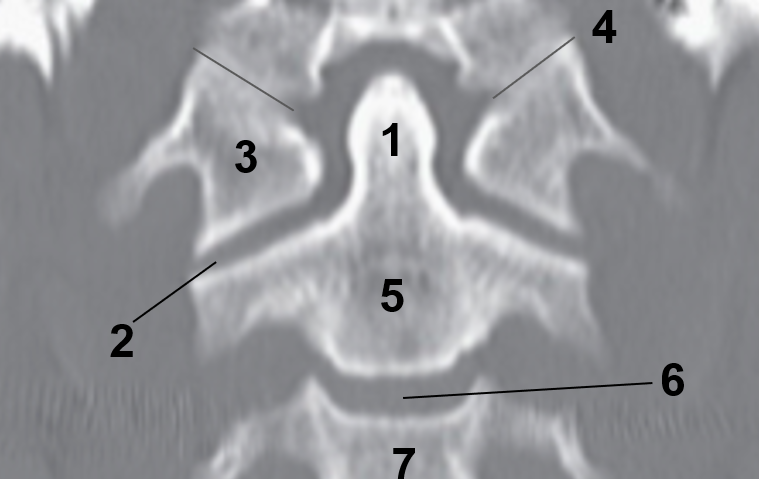

1

Transverse foramen

2

Anterior arch

3

Transverse Process

4

Posterior arch

5

Superior articular facet

6

Dens

7

Vertebral Foramen

1

Dens

2

Lateral Masses

3

Atlas

4

Atlanto-occipital joint

5

Body of the axis

6

C2-C3 Intervertebral disc

7

C3